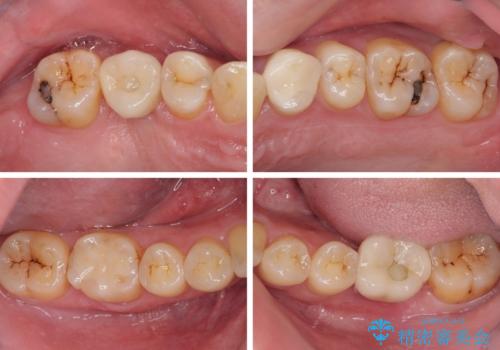

矯正治療を行いながら、欠損部はインプラントによる補綴治療を希望されたため、補助装置を用いたワイヤー矯正によりスペースを確保しながら歯列を整え、適宜インプラントを埋入していくこととしました。

下顎前歯にインプラントを2本埋入するのは非常に困難であり、どうしても歯肉位置に土台の金属色が見えてしまう仕上がりとなりました。無理をせずに1本のみの埋入とするか、ブリッジを提案しましたが、患者様の強い希望により、2本埋入することとなり、大変満足していただけました。